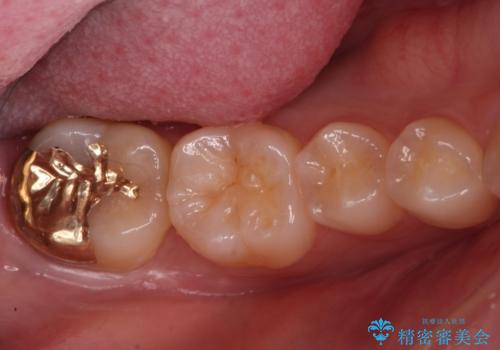

虫歯治療後、精度の良いゴールドアンレーへ

- 検査の結果虫歯が見つかった患者様です。

親知らずを抜歯してから虫歯を除去した後、ゴールドの詰め物で修復します。

比較的大きな虫歯でしたがゴールドでの修復にすることで歯の削る量を抑え、精度の高い治療を行うことができました。

親知らずの問題も同時に解決することで今後の虫歯リスクを抑えています。